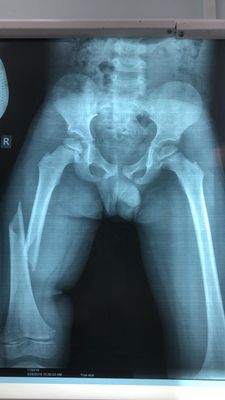

This 4-year old patient presented to the emergency room with a spiral displaced fracture of the right femur. He was running at school and tripped and fell.